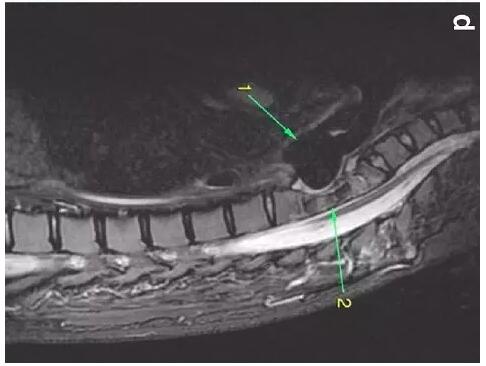

患者入住我院前行胸MRI已經(jīng)發(fā)現(xiàn)類似表現(xiàn)(圖d),當(dāng)時診斷為骨髓炎。

下圖箭頭1為氣切套管氣囊緊貼T1-4椎體水平,造成椎體前部受到侵蝕(箭頭2):